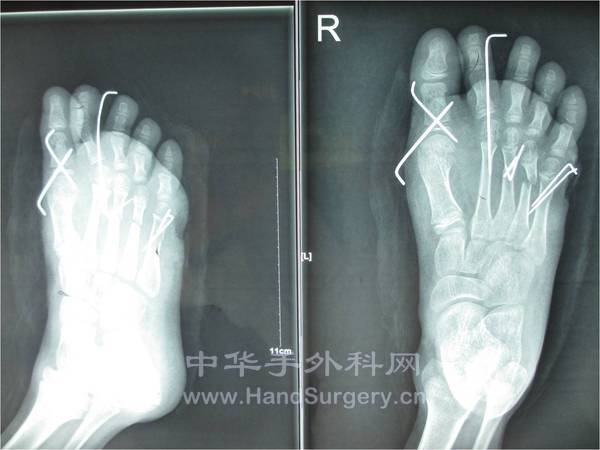

患者男性,8岁,于2013年2月23日因外伤在外院就诊,行:“清创,骨折内固定术及VSD负压吸引术”,术后VSD更换3次,并告知右小趾已坏死需截趾,患者拒绝遂转入我院,予以拆除VSD见小趾已坏死,告知患者次日手术,因右小趾已坏死需截除,创面需行皮瓣或人工皮覆盖。患者家属拒绝截趾,转回原医院。被告知需截除右足至第五跖骨,外露创面用小趾废弃皮覆盖后剩余创面植皮,患者家属遂崩溃,后再次来我院咨询就诊,考虑患者为小儿,第五跖骨头截除影响负重行走,遂收入院,于2013/3/25行皮瓣修复。术中见右第五跖骨表面已较多氧化、发黑,关节囊等已坏死,右小趾坏死。术中刮除右第五跖骨表面坏死骨,短缩右小趾至近节远端。目前术后第七天皮瓣顺利渡过危险期。

3月25日在麻醉下行股前外侧皮瓣修复创面术